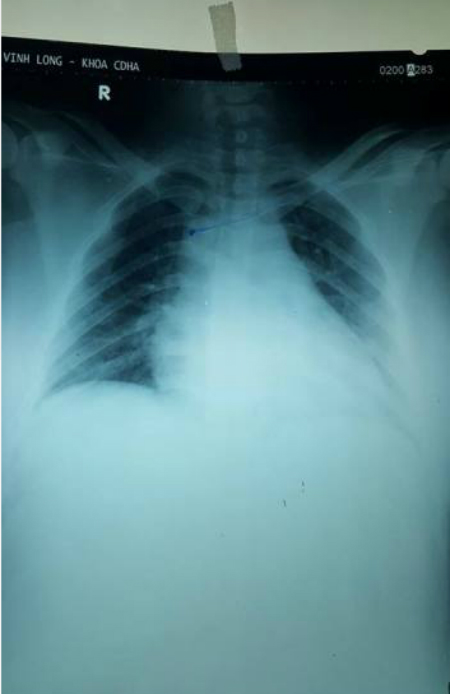

Chụp X-quang kiểm tra ống thông catheter tĩnh mạch trung tâm. Ảnh: Vnexpress |

Các bác sĩ đã quyết định đặt ống thông catheter tĩnh mạch trung tâm để tiến hành gây mê nội khí quản.